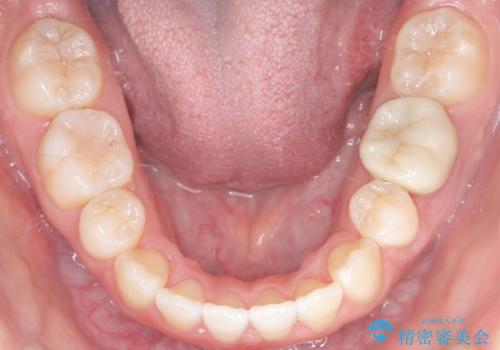

- 前歯のデコボコ(叢生)と、上下の歯が閉じない開口を主訴にご来院されました。精密な検査の結果、歯が並ぶスペースが不足しており、特に奥歯の咬み合わせが安定していないことが開口の原因と判明。患者様と相談し、上下左右の小臼歯を抜歯することでスペースを確保し、審美ワイヤー矯正で全体を整える治療計画を立案しました。これにより、見た目の改善だけでなく、機能的な咬み合わせも獲得することを目指します。

今回の矯正治療では、歯が並ぶスペースを確保するため、上下左右の小臼歯を抜歯しました。装置には目立ちにくい審美ワイヤーを使用し、見た目に配慮しながら治療を進めました。抜歯によってできたスペースを利用して歯を並べ、前歯のデコボコを解消。同時に、歯列全体を動かすことで、上下の歯がきちんと閉じる開口も改善しました。治療期間は約2年間。治療の結果、コンプレックスだった前歯のデコボコと開口が解消され、整った美しい歯並びと、しっかり咬める機能的な咬み合わせを獲得していただけました。